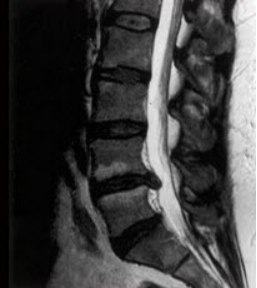

1、如图所示,低位腰麻是指阻滞平面在()

正确答案:T10以下

2、如图所示,硬膜外间隙的解剖特点,不正确的是()

正确答案:小儿硬膜外间隙与颅腔相通

3、如图示,脊髓的硬膜囊延伸到哪一部位()

正确答案:第2骶段

4、如图所示,对蛛网膜的描述哪项错误()

正确答案:为一层韧带

5、临床上常将感觉阻滞平面超过T4者称高位脊麻,T10平面以下者称低位脊麻。